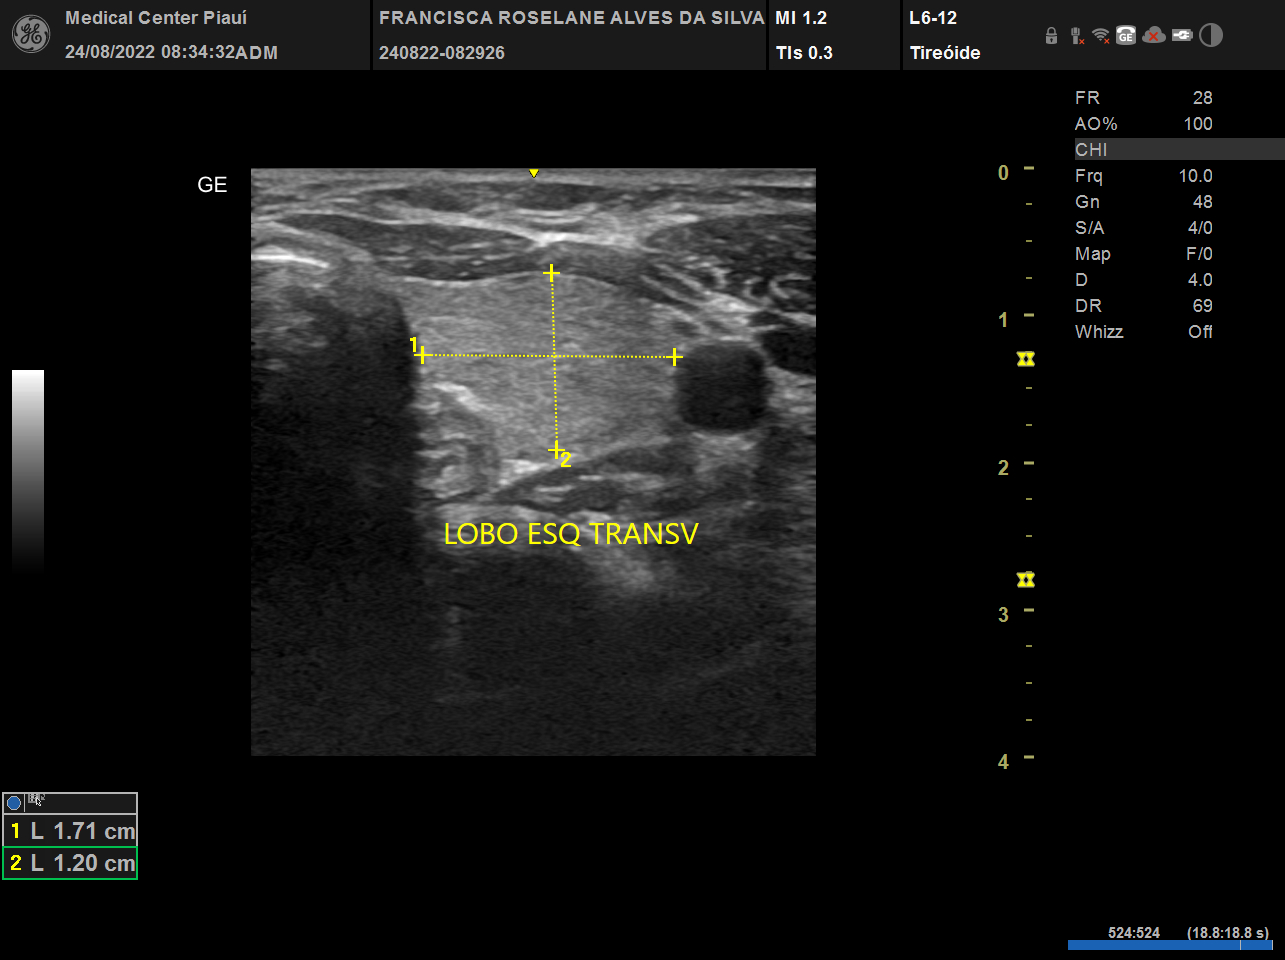

USG, TC e RN de tireoide